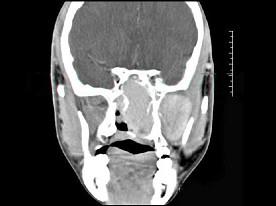

问题 男性,19岁,左侧鼻腔反复出血一年余,CT、MRI扫描如图所示,请选择最可能诊断 ( )

选项 A、鼻咽癌 B、鼻咽部淋巴瘤 C、鼻咽腔脓肿 D、鼻咽部青年纤维血管瘤 E、鼻息肉

答案 D